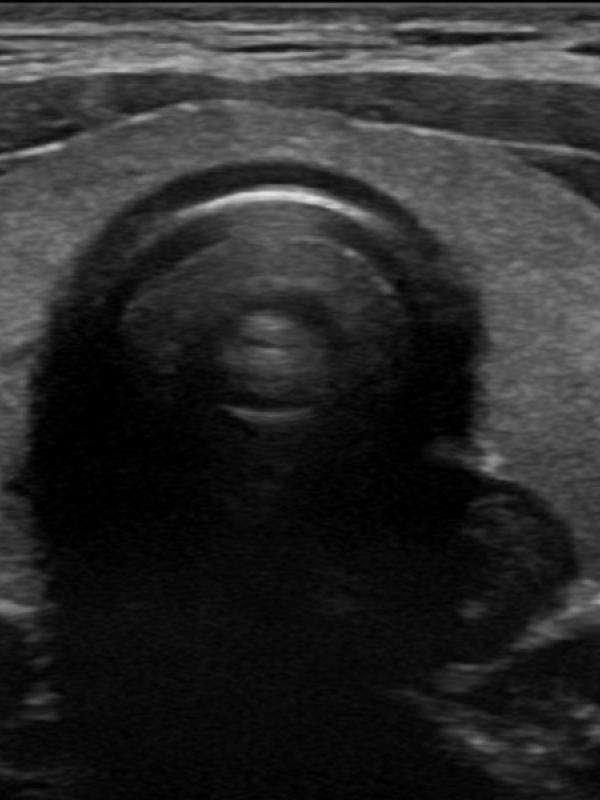

Scrotal ultrasound FAQ

Scrotal ultrasound

Ultrasound imaging is the primary diagnostic modality used to evaluate the scrotum/testicles. Referring providers will order a scrotal ultrasound for a number of reasons. The most common reasons are: testicular pain, a lump is discovered, or if a hernia is suspected. Undescended testis.

• Will the ultrasound of the scrotum and testicles be painful? No. The ultrasound exam will not be painful at all. The sonographer uses warm ultrasound gel and very light pressure from the transducer to image the testicles and scrotal contents.

• Is there any preparation required for a scrotal ultrasound exam? No, there is no preparation needed before having a scrotal ultrasound.

• Who interprets the scrotal exam? Sound Health Imaging contracts with Proscan Reading Services to read our exams. They are fellowship-trained, board-certified radiologists with subspecialty training.

• When and how will I get results? The scrotal ultrasound exam will be read by the radiologist within 24 hours of your study unless the study indicates need for results sooner. The results will be sent directly to your referring provider the week-day after your exam.

• How do I schedule my Scrotal ultrasound at Sound Health Imaging? A provider order is required for the scrotal ultrasound. When you see your health care provider, let them know you would like to have your ultrasound scheduled at Sound Health Imaging. Or, after you see your provider, you can call our office and make your ultrasound appointment and then bring your order with you at the time of exam.